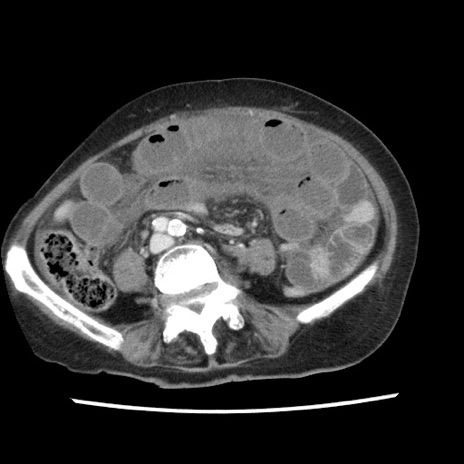

【症例】80歳代女性

【主訴】腹痛

【現病歴】8時間前から腹痛あり来院。

【既往歴】糖尿病、脂質異常症、子宮体癌にて子宮全摘術

【身体所見】意識清明・会話良好だが腹痛で苦悶様、全腹部にわたって反跳痛と圧痛あり

【データ】WBC 13600、CRP 0.14、LDH 224、CK 90